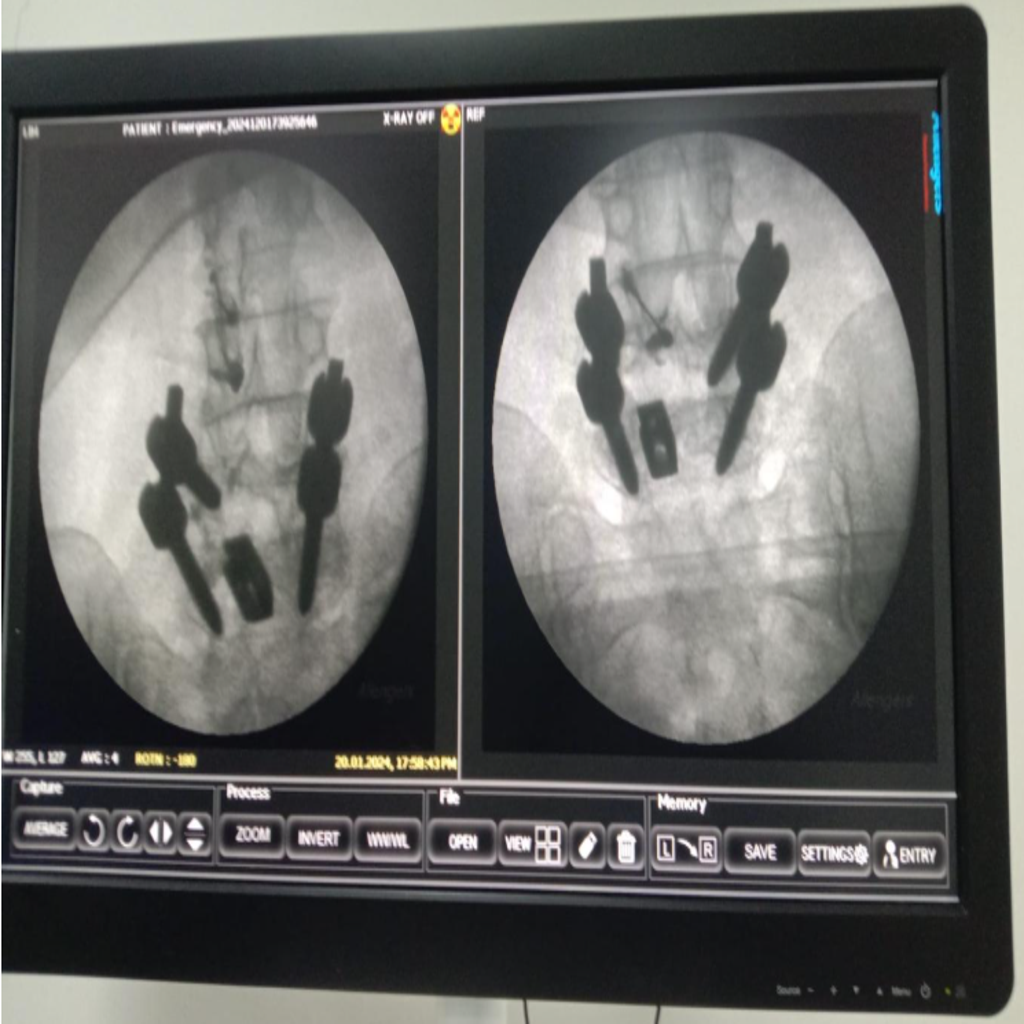

Fluoroscopy guided Intraarticular Facet joint Injection being carried out at Alleviate Pain Clinic, Bengaluru. Image Courtesy- Alleviate Pain Clinic

Image-guided precision treatments include:

- Lumbar facet joint injections for facet arthritis

- Medial branch blocks & radiofrequency ablation for chronic facet pain

- Sacroiliac joint injections for SI dysfunction

- Piriformis muscle injections (ultrasound-guided)

- Epidural or nerve root blocks for disc-related sciatica